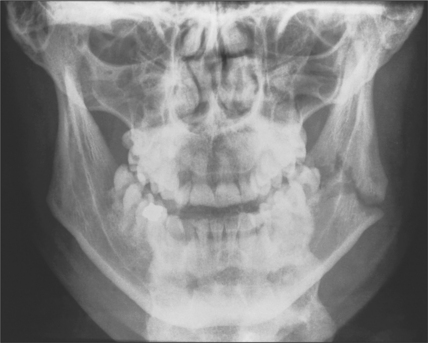

tooth-bearing areas of the jaws: orthopantomogram and posteroanterior (Figs 13.7, 13.8)

Fig. 13.7 Orthopantomogram of fractured mandible.